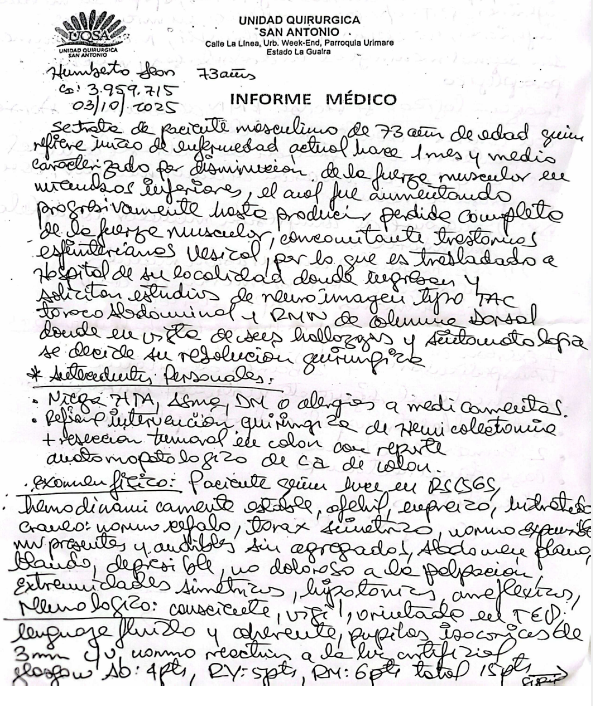

Paciente: Masculino, 73 años.

Antecedentes recientes: Desde hace 1 mes y medio presenta disminución progresiva de la fuerza en las piernas hasta llegar a una parálisis completa y pérdida de fuerza muscular. También tiene trastornos urinarios (dificultad para controlar la vejiga).

Antecedentes médicos: Operación previa por cáncer de colon (hemicolectomía por adenocarcinoma de colon).

Examen físico: Paciente consciente, con parálisis en ambas piernas (paraplejía), reflejos ausentes en miembros inferiores, alteración de esfínteres, pero sin signos meníngeos ni cerebelosos.

Estudios de imágenes: Resonancia magnética de columna dorsal: se observa una lesión tumoral que invade el canal medular, causando compresión de la médula espinal a nivel de las vértebras T4 y T5.

Diagnóstico: Síndrome de compresión medular completo, secundario a: Metástasis ósea de cáncer de colon con invasión medular. Metástasis pulmonar en ápice derecho.